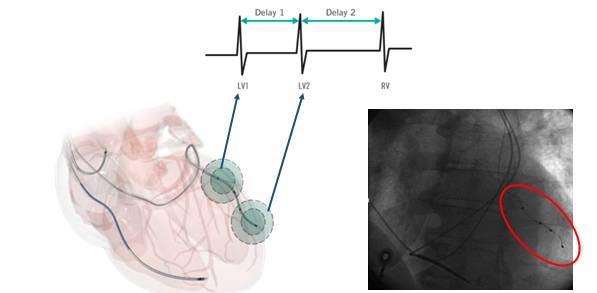

单电极多部位起搏 (MPP)

MPP is an upgraded form of CRT, which provides numerous alternative pacing sites and vectors, and involves the pacing of multiple sites within the same coronary sinus vein by means of a single quadripolar lead.

MPP改善双室电同步性

——入选10例患者的急性期观察

MPP改善左室机械同步性

MPP could shorten standard difference of time to peak contraction and early to late segment delay.

MPP改善急性血流动力学

MPP could provide extra hemodynamic advantages beyond the conventional CRT in most patients.

MPP长期随访结果

——12个月的随访结果

LV end-systolic volume, LV ejection fraction, and the NYHA class change in MPP group were remarkably improved compared with that of the conventional group after a 12-month-followup.

亚组分析:MPP与CRT无反应者

In CRT non-responders, MPP increased the dP/dt max and decrease the ventricular activation time.

亚组分析:MPP与缺血性心衰

The improvement of LV end-systolic volume, LV ejection fraction and the NYHA class was similar in patients with or without ischemic heart failure.

MPP的临床作用